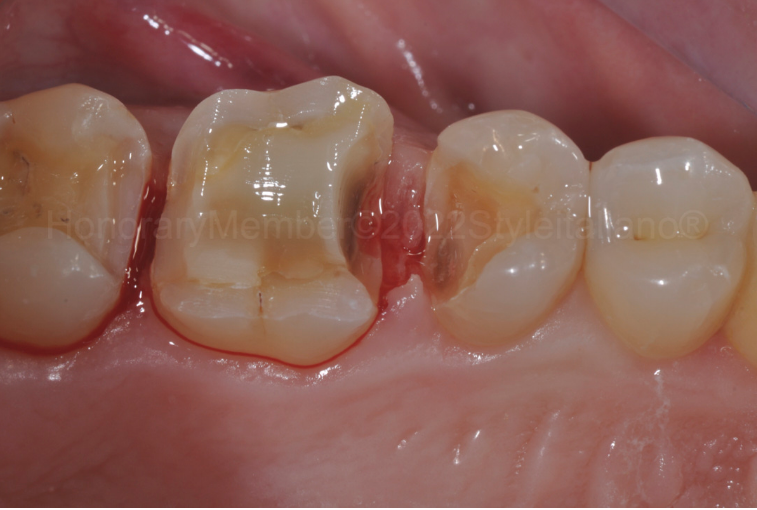

图二:在去除原修复体后,于25、26牙邻面龈壁可发现一些腐质,去除这些腐质,边缘深至龈下,邻接区无残留釉质,因此,决定使用树脂改良型玻璃离子重建边缘解剖结构,为什么呢?有以下几点原因。

-

边缘封闭的完整性可经受时间的考验。 -

纯树脂对龈沟内的酸性环境更敏感。 -

化学固化阶段材料应力较低。 -

与牙本质的自然粘接。 另一方面,树脂改良型玻璃离子具有较低的机械性能和电阻。